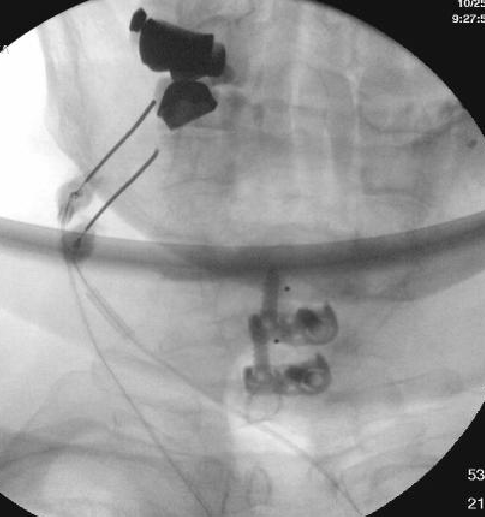

Nasty neuritis. This is 80 degrees 90 seconds.

These images look great. Sorry it happened? Steroid?

Lyrica Rx sent in, and we're starting it for chronic pain (and neuritis). She gets a shoulder scope in two weeks for a large RCT. I like antineuropathics (gabapentin 100mg HS or BID) perioperatively in general. I wish they were given 2 weeks before and after ALL orthopedic surgeries.

Dexamethasone given before RFA needles were removed.